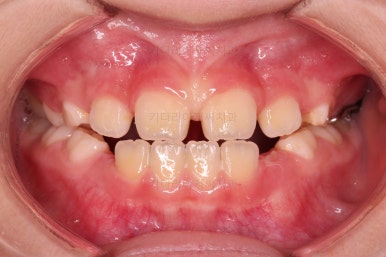

초진 시 입안의 모습입니다.

아래쪽 치열이 전반적으로 윗니보다 앞쪽에 위치한 전형적인 앵글씨 3급 부정교합인데요.

어금니에서부터 앞니까지 아랫니가 윗니보다 앞쪽에 위치하네요.

특히 앞니는 아랫니가 윗니보다 나와있는 "반대교합" 상태였고요.

또한 위아래로 겹침이 없고 떠있는 "개방교합" 상태였어요.

즉, 앵글씨 3급 부정교합 - 반대교합 - 개방교합 등 굉장히 복합적인 교합의 문제를 가진 환자였습니다.